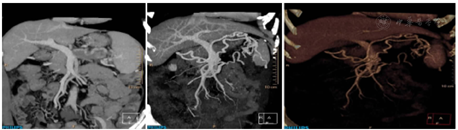

腹部CT三维重建示(图3):(1)胰尾所见,考虑胰腺恶性病变,胰腺癌可能性大。腹膜转移可能。左侧肾上腺转移可能;(2)网膜囊静脉曲张,考虑胰源性区域性门静脉高压所致,脾静脉局部显示欠佳。

2019年7月15日胃底粘液湖清亮,可见静脉曲张,直径0.3~0.4 cm,红色征阴性。胃体前壁及大弯侧可见静脉曲张,直径0.2~0.3 cm,红色征阴性。内镜下诊断:食管多发白斑、食管裂孔疝;慢性萎缩性胃炎(C2);胃静脉曲张(Lgfb D1.0Rf0)。